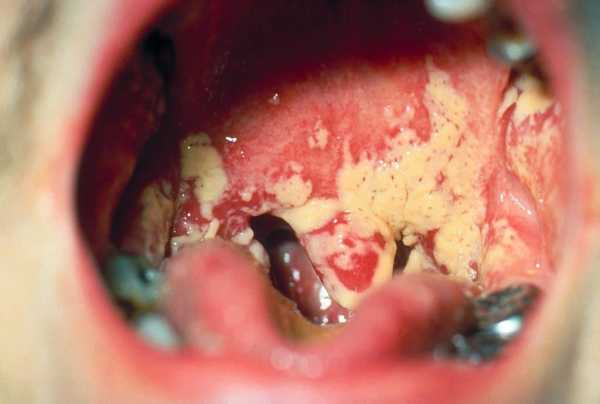

ΡΠΎΡΠΎ: ΠΏΡΠΎΡΠ²Π»Π΅Π½ΠΈΠ΅ Π³ΡΠΈΠ±ΠΊΠ° Π² Π³ΠΎΡΠ»Π΅

Π’Π²ΠΎΡΠΎΠΆΠΈΡΡΡΠΉ Π½Π°Π»Π΅Ρ Π½Π° ΡΠ»ΠΈΠ·ΠΈΡΡΠΎΠΉ ΠΎΠ±ΠΎΠ»ΠΎΡΠΊΠ΅ ΡΠ²Π»ΡΠ΅ΡΡΡ ΠΎΡΠ»ΠΈΡΠΈΡΠ΅Π»ΡΠ½ΡΠΌ ΠΏΡΠΈΠ·Π½Π°ΠΊΠΎΠΌ Π³ΡΠΈΠ±ΠΊΠ° Π² Π³ΠΎΡΠ»Π΅. ΠΡΠ΄Π΅Π»Π΅Π½ΠΈΡ ΡΠΊΠ°ΠΏΠ»ΠΈΠ²Π°ΡΡΡΡ ΠΈ Π²ΠΎΠ·Π²ΡΡΠ°ΡΡΡΡ Π½Π°Π΄ ΠΏΠΎΠ²Π΅ΡΡ Π½ΠΎΡΡΡΡ ΠΌΠΈΠ½Π΄Π°Π»ΠΈΠ½, Π·Π°Π΄Π½Π΅ΠΉ ΡΡΠ΅Π½ΠΊΠΈ Π³Π»ΠΎΡΠΊΠΈ, ΡΠ·ΡΠΊΠ°, Π½Π΅Π±Π½ΡΡ Π΄ΡΠΆΠ΅ΠΊ. ΠΠ΅Π»ΡΠ΅ ΡΠΎΡΠΊΠΈ ΠΈ ΠΊΡΡΠΏΠΈΠ½ΠΊΠΈ ΠΎΡΡΠ΅ΡΠ»ΠΈΠ²ΠΎ Π²ΠΈΠ΄Π½Ρ Π½Π° ΡΡΠΊΠΎ-ΠΊΡΠ°ΡΠ½ΠΎΠΉ Π²ΠΎΡΠΏΠ°Π»Π΅Π½Π½ΠΎΠΉ ΡΠ»ΠΈΠ·ΠΈΡΡΠΎΠΉ ΠΎΠ±ΠΎΠ»ΠΎΡΠΊΠ΅. ΠΡΠ΄Π΅Π»Π΅Π½ΠΈΡ ΠΌΠΎΠ³ΡΡ ΠΈΠΌΠ΅ΡΡ Π²ΠΈΠ΄ ΠΏΠ»Π΅Π½ΠΎΠΊ ΠΈΠ»ΠΈ Π±Π»ΡΡΠ΅ΠΊ, ΡΠΊΠ»ΠΎΠ½Π½ΡΡ ΠΊ ΡΠ»ΠΈΡΠ½ΠΈΡ. ΠΠ°Π»Π΅Ρ ΡΠ½ΠΈΠΌΠ°Π΅ΡΡΡ Ρ Π±ΠΎΠ»ΡΡΠΈΠΌ ΡΡΡΠ΄ΠΎΠΌ, Π° ΠΏΠΎΠ΄ Π½ΠΈΠΌ ΠΎΠ±ΡΠ°Π·ΡΡΡΡΡ ΡΡΠΎΠ·ΠΈΠΈ ΠΈ ΡΠ·Π²Ρ. ΠΡΠΈ ΠΎΡΡΡΡΡΡΠ²ΠΈΠΈ ΡΠ²ΠΎΠ΅Π²ΡΠ΅ΠΌΠ΅Π½Π½ΠΎΠ³ΠΎ ΠΈ Π°Π΄Π΅ΠΊΠ²Π°ΡΠ½ΠΎΠ³ΠΎ Π»Π΅ΡΠ΅Π½ΠΈΡ ΠΈΠ½ΡΠ΅ΠΊΡΠΈΡ ΡΠ°ΡΠΏΡΠΎΡΡΡΠ°Π½ΡΠ΅ΡΡΡ Π½ΠΈΠΆΠ΅ ΠΈ ΠΏΠΎΡΠ°ΠΆΠ°Π΅Ρ ΠΏΠΈΡΠ΅Π²ΠΎΠ΄, ΠΎΡΠ³Π°Π½Ρ Π΄ΡΡ Π°ΡΠ΅Π»ΡΠ½ΠΎΠΉ ΠΈ ΠΏΠΈΡΠ΅Π²Π°ΡΠΈΡΠ΅Π»ΡΠ½ΠΎΠΉ ΡΠΈΡΡΠ΅ΠΌ.